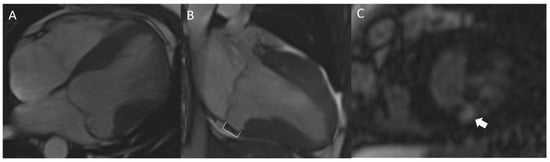

- Kitkungvan, D.; Nabi, F.; Kim, R.J.; Bonow, R.O.; Khan, M.A.; Xu, J.; Little, S.H.; Quinones, M.A.; Lawrie, G.M.; Zoghbi, W.A.; et al. Myocardial fibrosis in patients with primary mitral regurgitation with and without prolapse. J. Am. Coll. Cardiol. 2018, 72, 823–834. [Google Scholar] [CrossRef]

- Constant Dit Beaufils, A.-L.; Huttin, O.; Jobbe-Duval, A.; Senage, T.; Filippetti, L.; Piriou, N.; Cueff, C.; Venner, C.; Mandry, D.; Sellal, J.-M.; et al. Replacement Myocardial Fibrosis in Patients With Mitral Valve Prolapse: Relation to Mitral Regurgitation, Ventricular Remodeling, and Arrhythmia. Circulation 2021, 143, 1763–1774. [Google Scholar] [CrossRef] [PubMed]

- Bui, A.H.; Roujol, S.; Foppa, M.; Kissinger, K.V.; Goddu, B.; Hauser, T.H.; Zimetbaum, P.J.; Ngo, L.H.; Manning, W.J.; Nezafat, R.; et al. Diffuse myocardial fibrosis in patients with mitral valve prolapse and ventricular arrhythmia. Heart 2017, 103, 204–209. [Google Scholar] [CrossRef] [PubMed] [Green Version]

- Pradella, S.; Grazzini, G.; Brandani, M.; Calistri, L.; Nardi, C.; Mori, F.; Miele, V.; Colagrande, S. Cardiac magnetic resonance in patients with mitral valve prolapse: Focus on late gadolinium enhancement and T1 mapping. Eur. Radiol. 2019, 29, 1546–1554. [Google Scholar] [CrossRef] [PubMed]

- Han, Y.; Peters, D.C.; Salton, C.J.; Bzymek, D.; Nezafat, R.; Goddu, B.; Kissinger, K.V.; Zimetbaum, P.J.; Manning, W.J.; Yeon, S.B. Cardiovascular magnetic resonance characterization of mitral valve prolapse. JACC Cardiovasc. Imaging 2008, 1, 294–303. [Google Scholar] [CrossRef] [PubMed] [Green Version]

- Han, H.-C.; Parsons, S.A.; Curl, C.L.; Teh, A.W.; Raaijmakers, A.J.A.; Koshy, A.N.; Leong, T.; Burrell, L.M.; O’Donnell, D.; Vohra, J.K.; et al. Systematic quantification of histologic ventricular fibrosis in isolated mitral valve prolapse and sudden cardiac death. Heart Rhythm 2021, 18, 570–576. [Google Scholar] [CrossRef]

- Fulton, B.L.; Liang, J.J.; Enriquez, A.; Garcia, F.C.; Supple, G.E.; Riley, M.P.; Schaller, R.D.; Dixit, S.; Callans, D.J.; Marchlinski, F.E.; et al. Imaging characteristics of papillary muscle site of origin of ventricular arrhythmias in patients with mitral valve prolapse. J. Cardiovasc. Electrophysiol. 2018, 29, 146–153. [Google Scholar] [CrossRef]

- Pavon, A.G.; Arangalage, D.; Pascale, P.; Hugelshofer, S.; Rutz, T.; Porretta, A.P.; Le Bloa, M.; Muller, O.; Pruvot, E.; Schwitter, J.; et al. Myocardial extracellular volume by T1 mapping: A new marker of arrhythmia in mitral valve prolapse. J. Cardiovasc. Magn. Reson. 2021, 23, 102. [Google Scholar] [CrossRef]